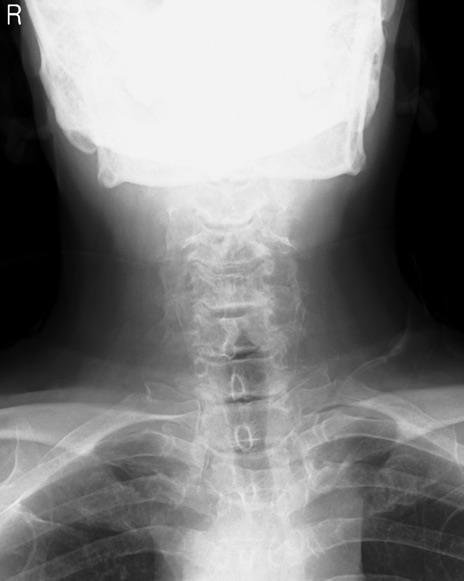

【整形】TIPS症例7 頚椎レントゲン(正面像)

【症例】60歳代男性

【主訴】両手のしびれ

【現病歴】15年前より右手のしびれあり。4ヶ月前から左手のしびれあり。最近、症状増悪あり。

【身体所見】BTR+/+、BRR+/+、TTR+/+、PTR ++/++、ATR ++/++、Babinski-/-

頚椎レントゲン